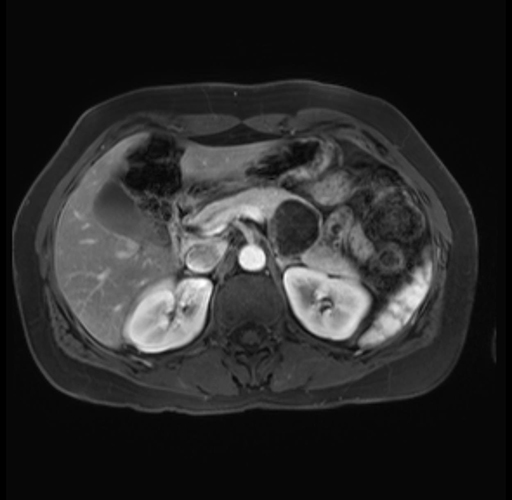

Imaging Analysis

Look through the patient's CT scan to identify any areas of concern for the necessary procedure.

Based on your CT findings, which issue(s) are present and would give reason for "planned slowing down moment(s)" in this case?